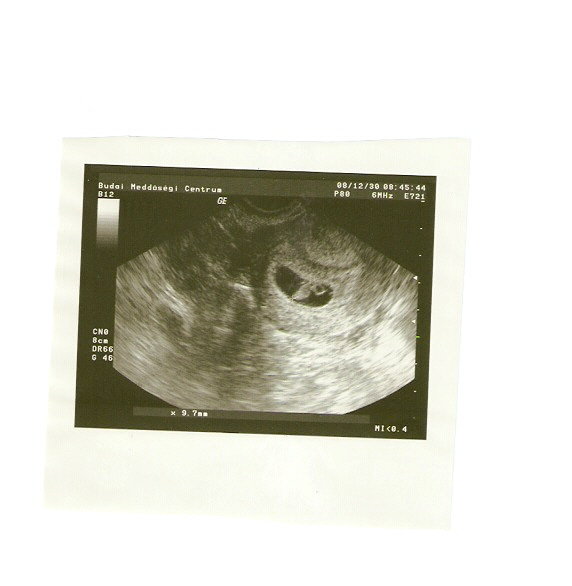

Kicsit viszontagságos volt, mert Jb-ben nem voltak hajlandóak megnézni, illetve úgy gondolták, hogy várjak egy fél napot, pedig megígérték,hogy a délelőtt megnézik.

Így apa telefonon felhívta az egri kórházat, hogy megnéznének-e uhun. Azt mondták igen, de egy órán belül érjünk oda. Hát sikerült.

Nagyon kedves nő nézett Egerben, hasi ultrahangot csinált, és

olyan szívhang volt, hogy zengett bele a szoba, majdnem leugrottam örömömben az ágyról.

Azt mondta a baba pont olyan, mint lennie kell, 5mm és nincs sehol bevérzés körülötte.

Az ultrahangos nő mondta nekem, hogy először mindig hasi uhu-t kell csinálni, hüvelyi uhu csak akkor indokolt, ha az a kérdés, hogy él-e a baba, és azt hasiból nem lehetne eldönteni, és a lelkemre kötötte, hogy ha egy mód van rá, a 12. heti vizsgálat kivételével ne engedjem, hogy hüvelyi uhu-t csináljanak, mert az olyan a babának, mintha mikrosütőbe tennék... (mint kiderült, ő az egyik szerzője az ultrahangos tankönyveknek is, szóval nem csak beszélt a világba, hanem ért hozzá. - egyébként a saját menyének még a 12. héten sem csinált hüvelyi uhut.)